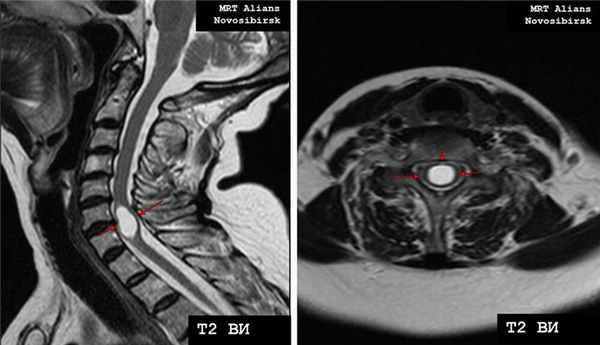

Рис. 4. МРТ шейного отдела позвоночника - гидросирингомиелия.